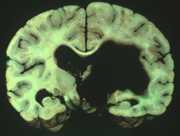

13